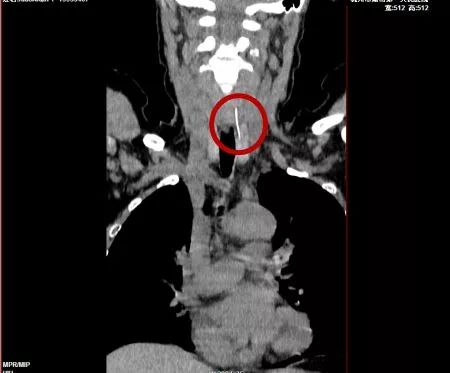

医生再次仔细阅片,发现上段食管壁左前方有一个亮点,再循着亮点往外侧软组织看去,好几个层面都有,竟然是连着的一条索状高密度影。

鱼刺

原来李大姐的鱼刺已经刺破了食管,扎进了颈部软组织及左侧甲状腺内,并且已经引起了炎症。如果不马上取出鱼刺,一方面,颈部炎症会扩散,变得难以控制,另一方面,如果鱼刺扎破颈动脉,后果不堪设想。

因为李大姐的鱼刺已经不在食管内了,医生在全麻手术下从颈部切开皮肤,终于在食管、气管和甲状腺的夹缝中找到并取出了李大姐的鱼刺。但因为李大姐的部分甲状腺已经被刺得发炎溃烂,只能切除。目前李大姐的咽痛已经缓解了,接下来还需要等食管的破口及颈部的切口愈合。